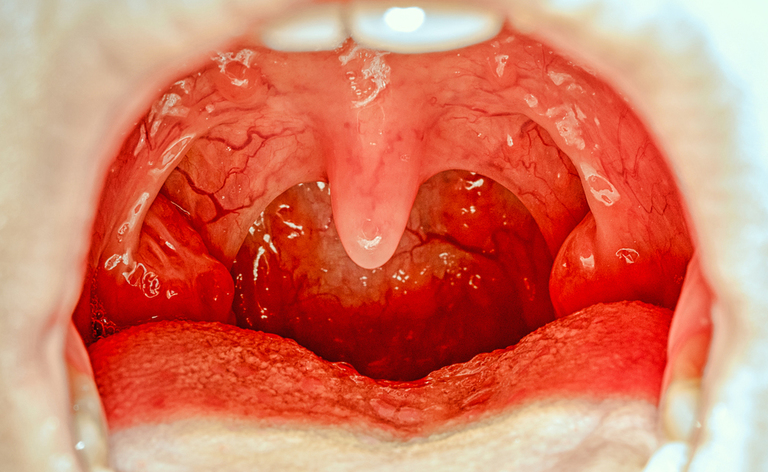

A cosa serve l’ugola: beh, non è ancora molto chiaro. Ciò che è certo è che quando si infiamma tende a gonfiarsi e a dare molto fastidio.